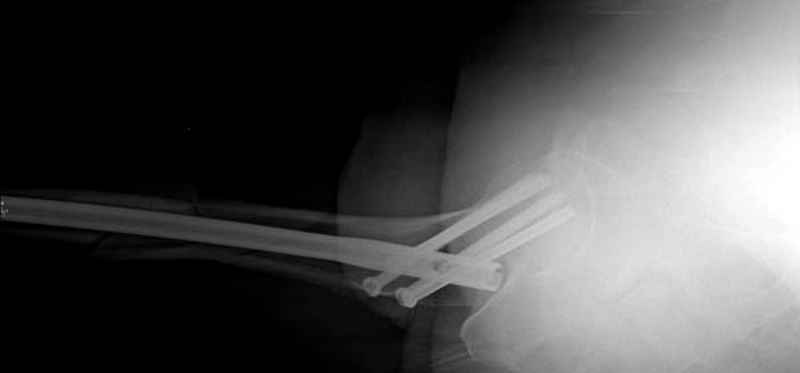

Для профилактики дальнейшего раскола в шейке предварительно во время проксимального рассверливания спереди и сзади провели временные спицы, которые в дальнейшем были заменены на шурупы (miss nail method)